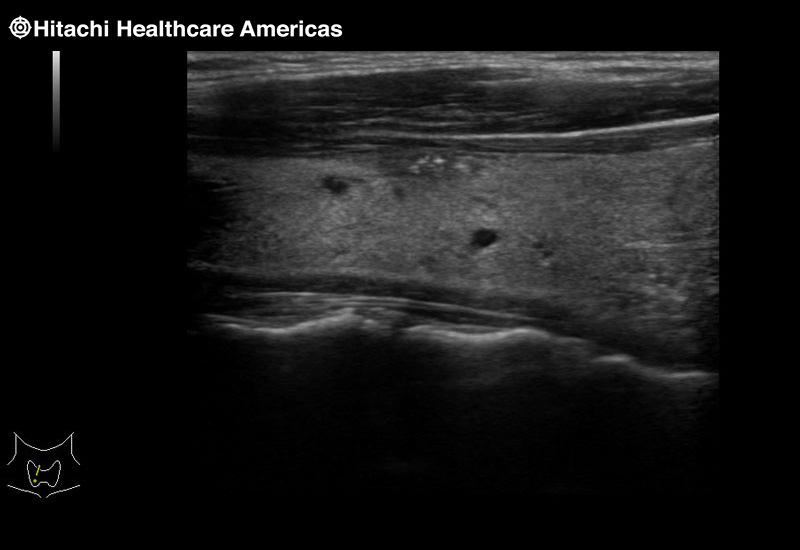

Superior guidance for all applications

Fujifilm Healthcare Americas is committed to designing tools that help surgeons navigate inside the human body and provide the necessary information to immediately make critical surgical decisions.

Fujifilm Healthcare's dedication to Surgeons provides outstanding ultrasound technology, professional support and the specialized tools necessary to best perform comprehensive real-time ultrasound imaging in Breast Surgery, General Surgery, Laparoscopic Surgery, Neurosurgery, Robotic Surgery and Surgical Oncology.

Imaging Clearly Defined

State-of-the-art digital architecture and advanced imaging features to redefine the capabilities of surgical ultrasound.